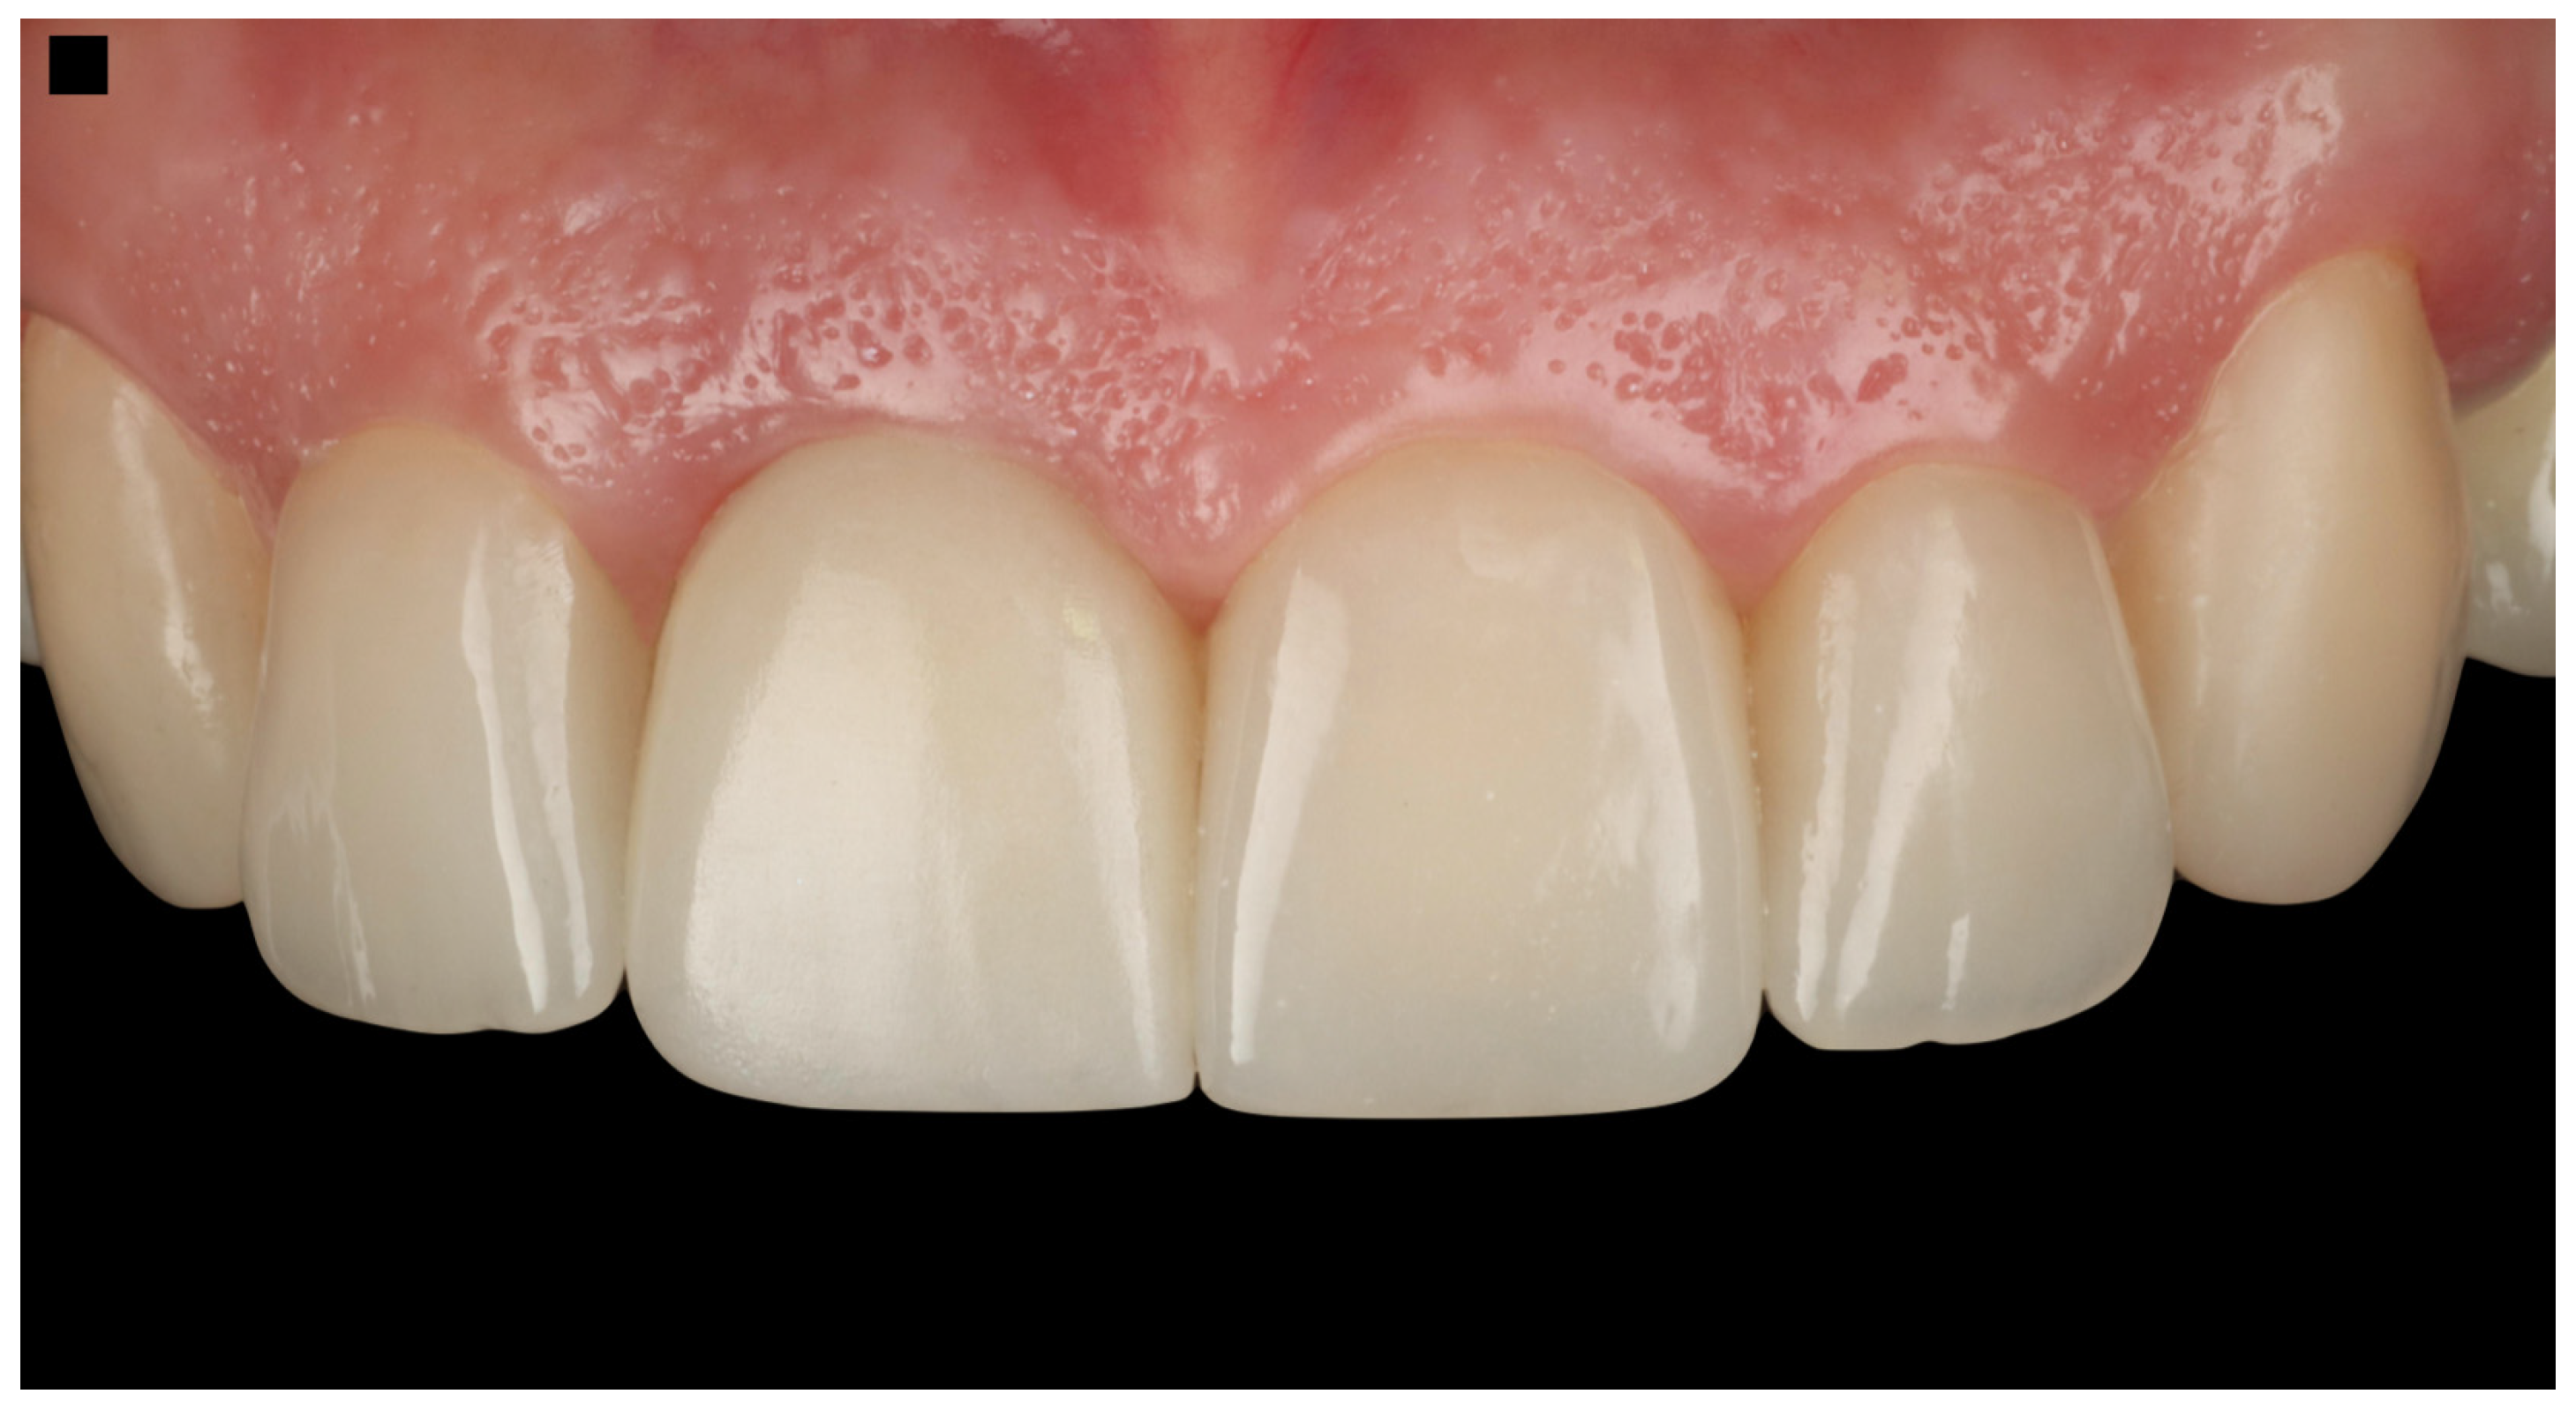

The patient expressed complete satisfaction with the final restorations, praising the natural shade and shape of the teeth. To protect the restorations from potential damage, the patient was provided with a custom-made night guard. Detailed oral hygiene instructions were given, emphasizing the importance of maintaining the health of the restorations and surrounding tissues. The patient was scheduled for regular follow-up visits every six months for professional dental prophylaxis and to monitor the condition of the restorations and periodontal tissues (Figure 10). At the three-year follow-up visit, the patient was still satisfied with the outcome.

Figure 10.

Final restorations.

The workflow performed in this case illustration successfully addressed the patient’s esthetic and functional needs. The initial three-dimensional planning, including a detailed CBCT analysis, allowed for precise treatment preparation. This was followed by atraumatic tooth extraction and immediate implant placement using a surgical guide. The placement of a screw-retained provisional restoration and the subsequent final restoration were meticulously executed, resulting in a predictable and satisfactory outcome. The restorations on the adjacent teeth significantly enhanced the patient’s smile, improving overall symmetry, color, and shape. Additionally, the patient was provided with a custom-made occlusal guard to protect the restorations during nighttime grinding or clenching.

The Pink Esthetic Score (PES) is a system used to evaluate the esthetic outcomes of soft tissues surrounding dental implants, particularly in the anterior region of the mouth. It is a well-accepted method in the literature for assessing treatment success [47]. The PES evaluates five variables: mesial and distal papilla, curvature of the gingival margin, level of the gingival margin, root convexity, and scar formation. Each variable is scored on a 0–1–2 scale, where 2 represents the best outcome and 0 the poorest. The maximum score is 14, with scores of 11 or above generally considered excellent, scores between 8 and 11 deemed acceptable, and scores below 8 considered poor. Based on the PES system, the results of the case presented in this study provide a score of 12, which is considered an excellent result (Figure 11).

The follow-up period for this case illustration is three years. At this stage, the patient remains satisfied with the functional and esthetic outcomes of the implant therapy provided. However, it is important to note that three years is a relatively short period to deem the treatment a long-term success. The patient has been educated on the importance of maintaining good oral hygiene and attending regular follow-up evaluation appointments. The clinical workflow, showcasing the key steps in the treatment process, is summarized in Figure 12. This workflow demonstrates the careful integration of planning, surgical precision, and restorative excellence in achieving the desired patient outcomes.